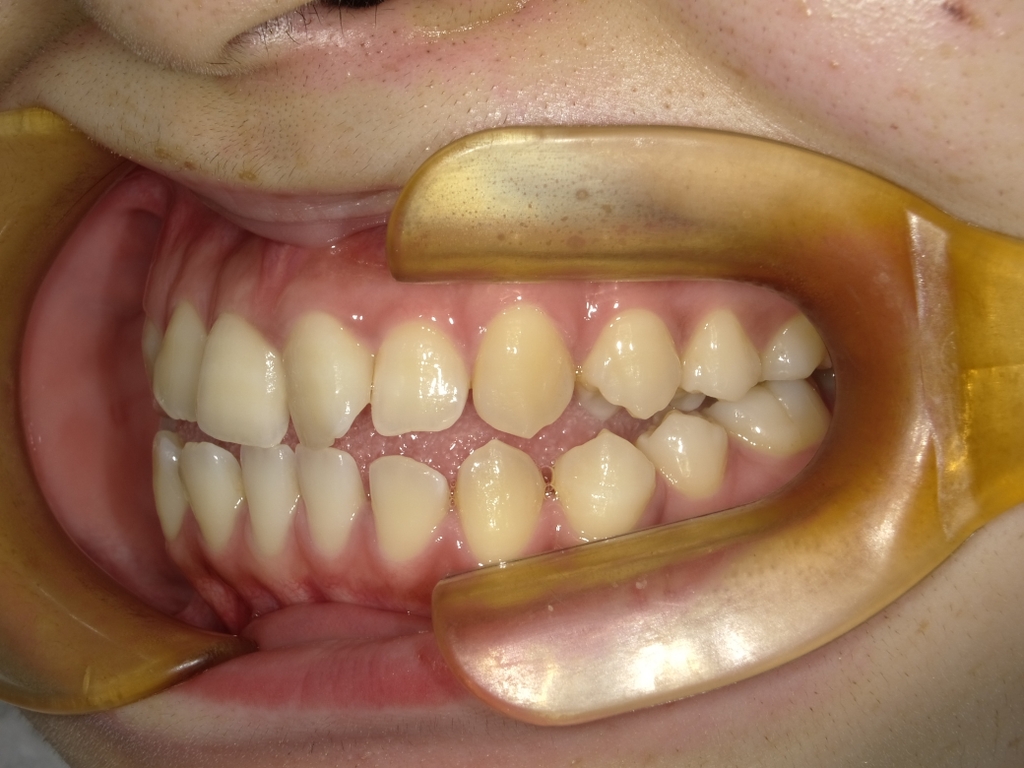

⏳ 矯正の期間はどのくらい?平均は「2〜3年」

一般的な成人矯正(全体矯正)の治療期間は、約2〜3年が目安です。

これはワイヤー矯正・マウスピース矯正のどちらでも大きな違いはありません。